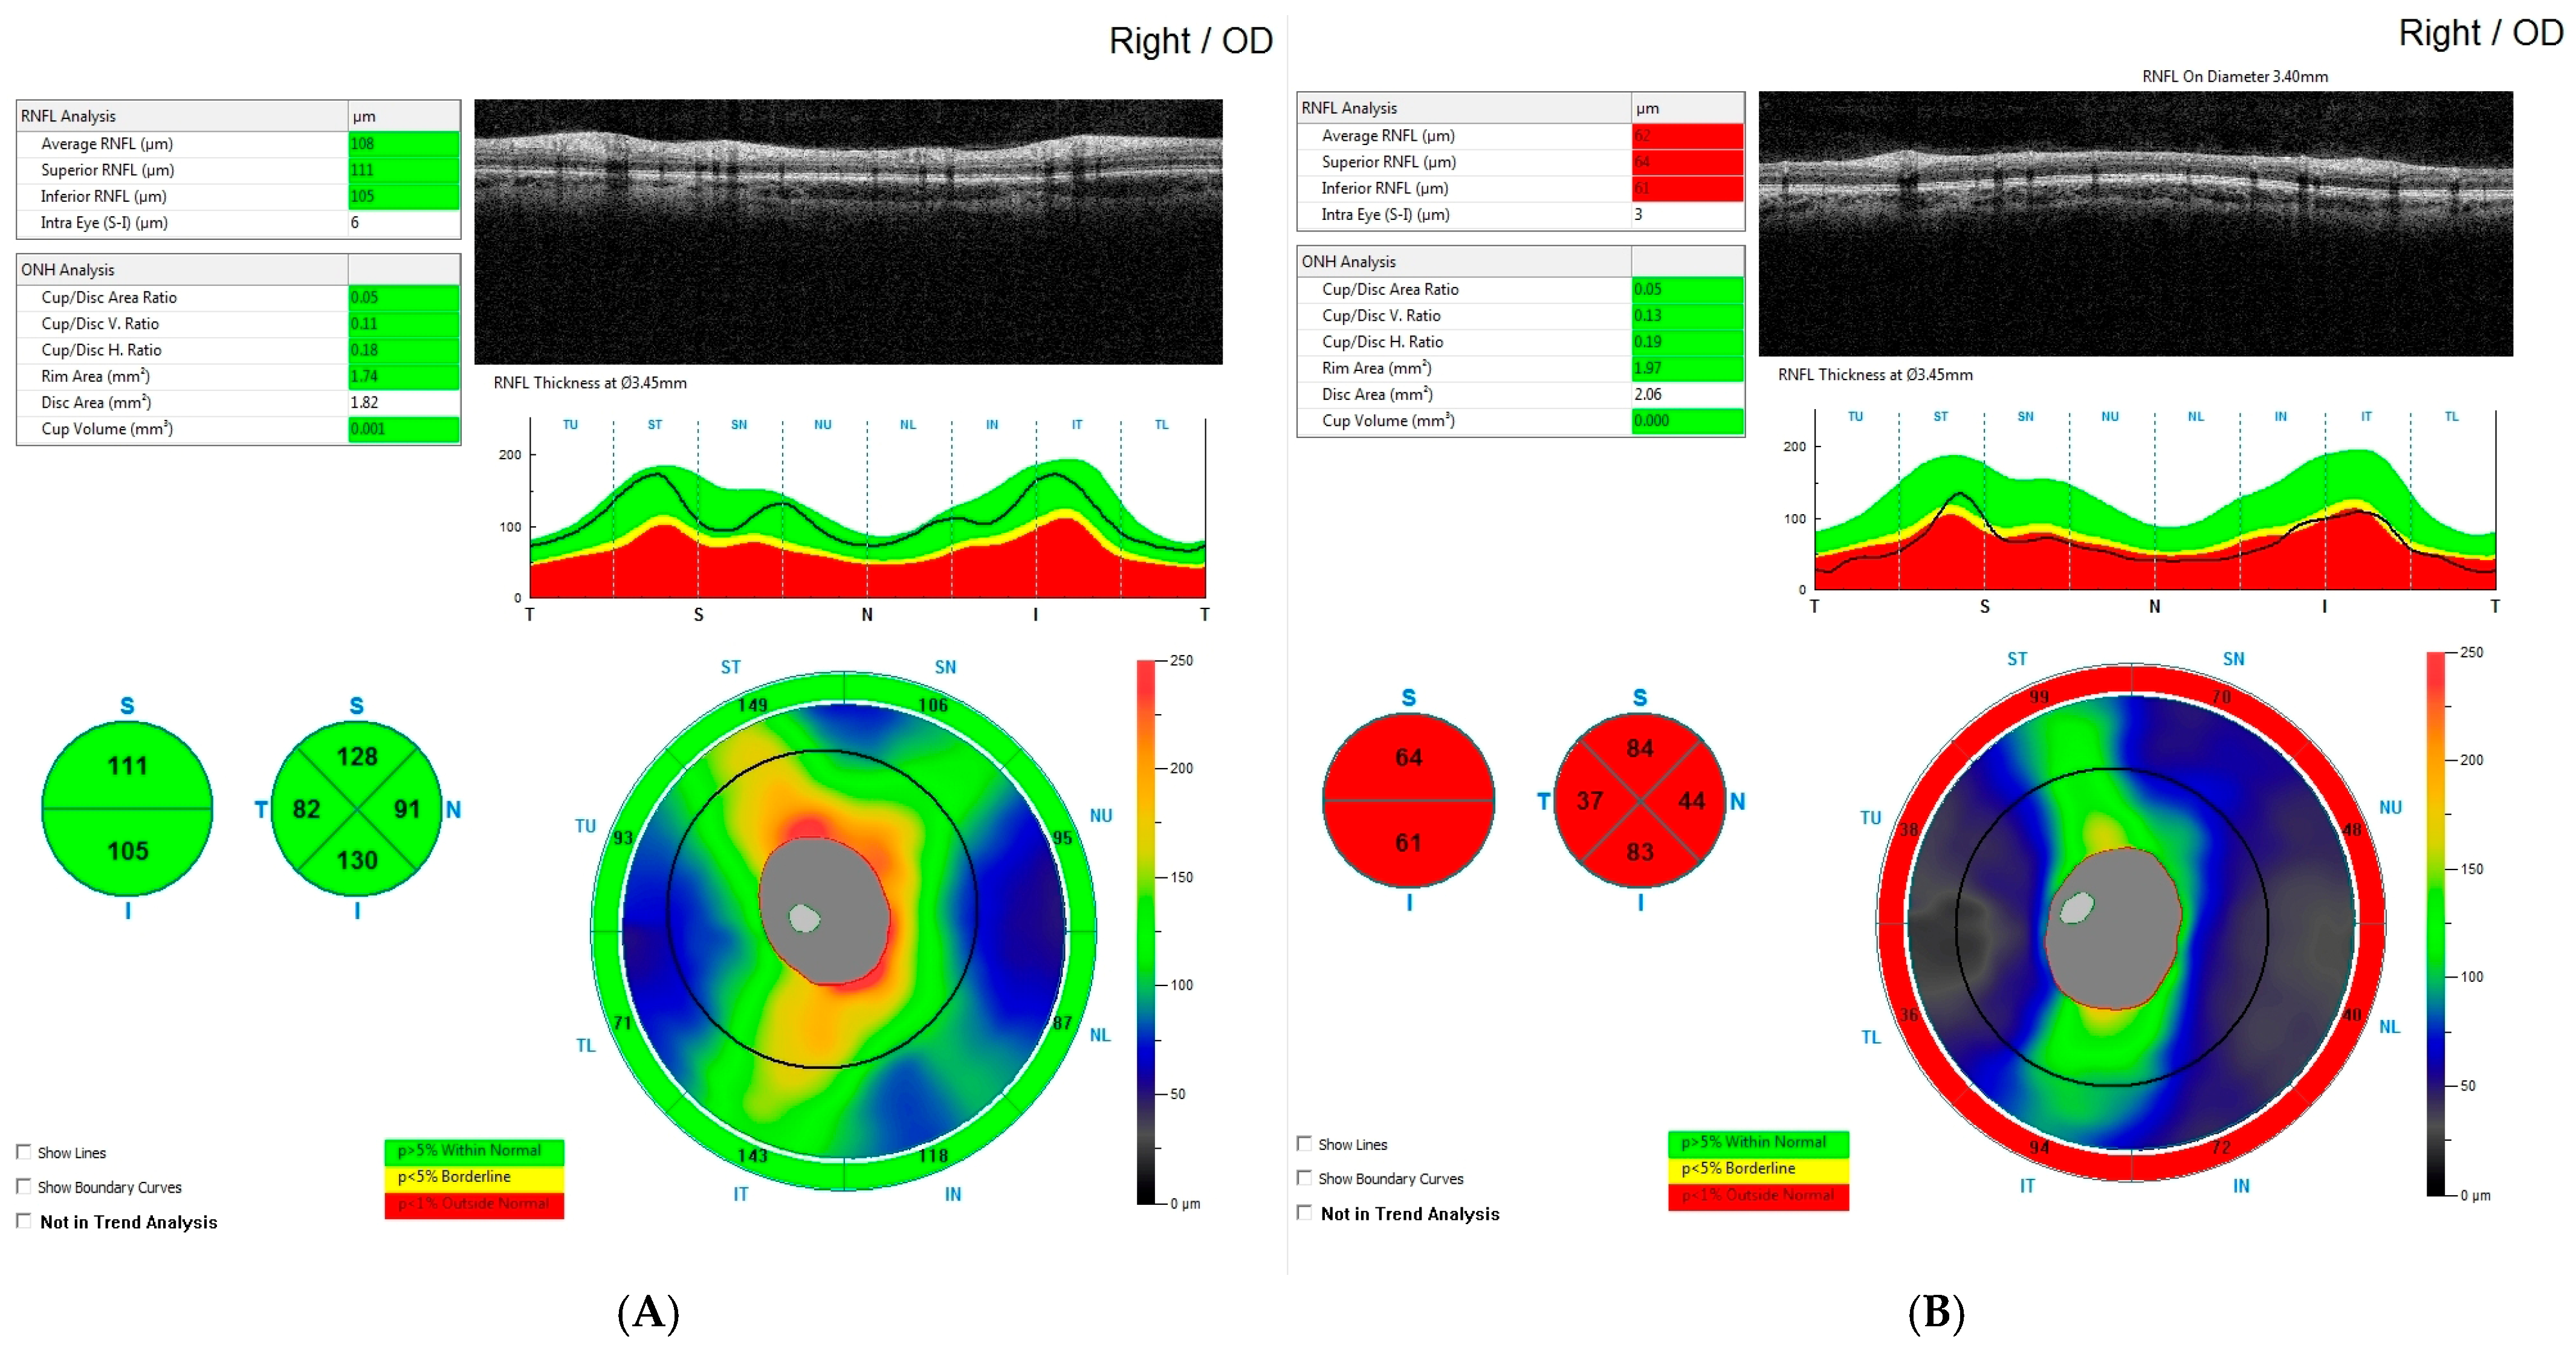

- Rakusiewicz-Krasnodębska, K.; Bogusz-Wójcik, A.; Moszczyńska, E.; Jaworski, M.; Kowalczyk, P.; Hautz, W. Evaluation of the Effect of Optic Nerve Compression by Craniopharyngioma on Retinal Nerve Fiber Layer Thickness in Pediatric Patients. Cancers 2025, 17, 2574. [Google Scholar] [CrossRef]